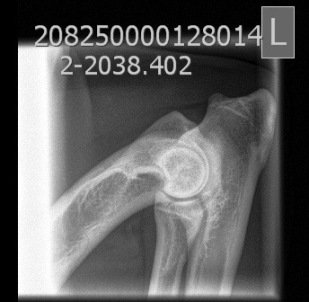

HD: A/A

AD: 0/0